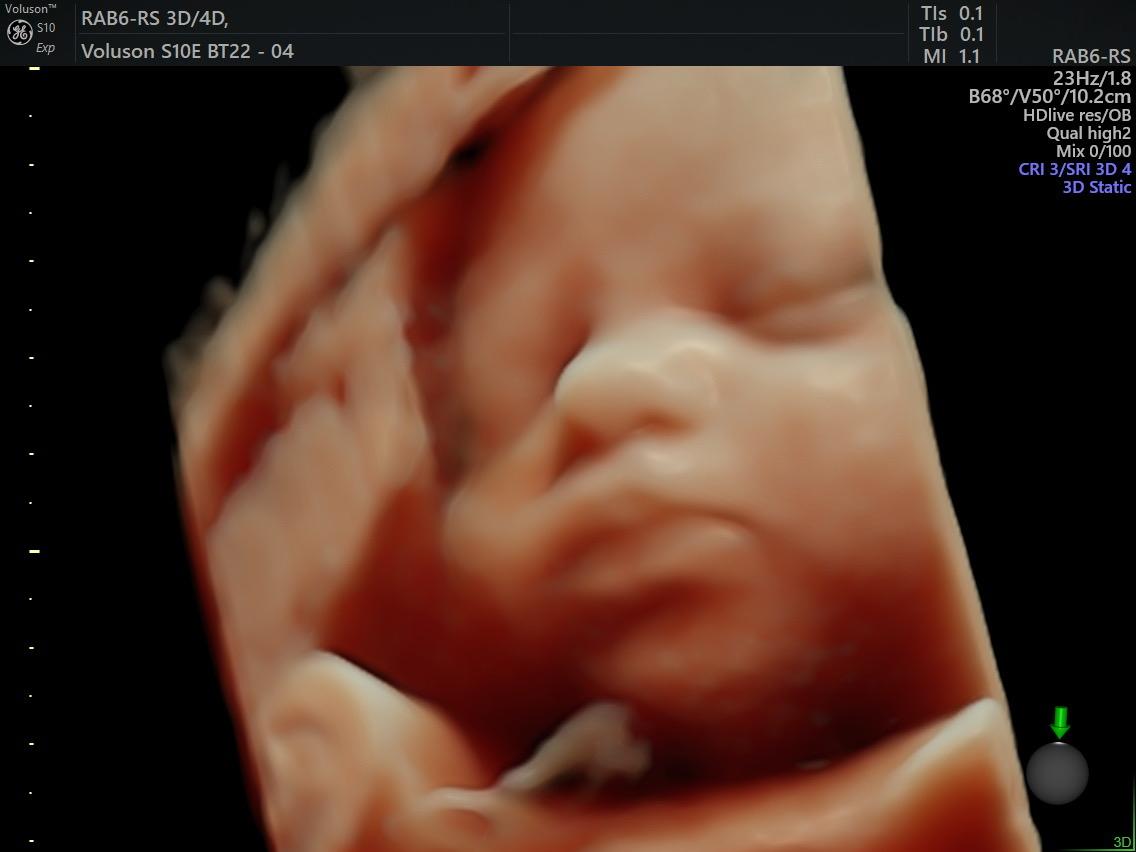

Fetal Medicine

Ultra Sound

Gallery

Images

Photos